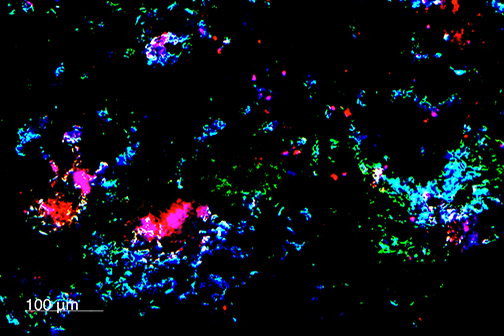

LSU Health New Orleans Researchers Discover a Key Failure in AMD that May Lead to Progression & Vision Loss

Research led by Nicolas Bazan, MD, PhD, Boyd Professor, Ernest C. and Yvette C. Villere Chair for the Study of Retinal Degeneration, and Director of the Neuroscience Center of Excellence at LSU Health New Orleans School of Medicine, suggests that age-related macular degeneration (AMD) decreases an essential fatty acid, preventing the formation of a class of protective molecules and reducing repair potential. The discovery may also open new therapeutic avenues for AMD. More

LSU Health New Orleans Develops New Human Cell Line to Study Blinding Eye Disorders

Under the direction of Boyd Professor Nicolas Bazan, MD, PhD, scientists at LSU Health New Orleans Neuroscience Center of Excellence have developed a new, experimental human cell line from retinal pigment epithelial cells. Called ABC, these cells so closely resemble and retain the properties of native retinal pigment epithelial (RPE) cells, the research team has shown that they are a reliable cell system to study retinal degenerative diseases. More